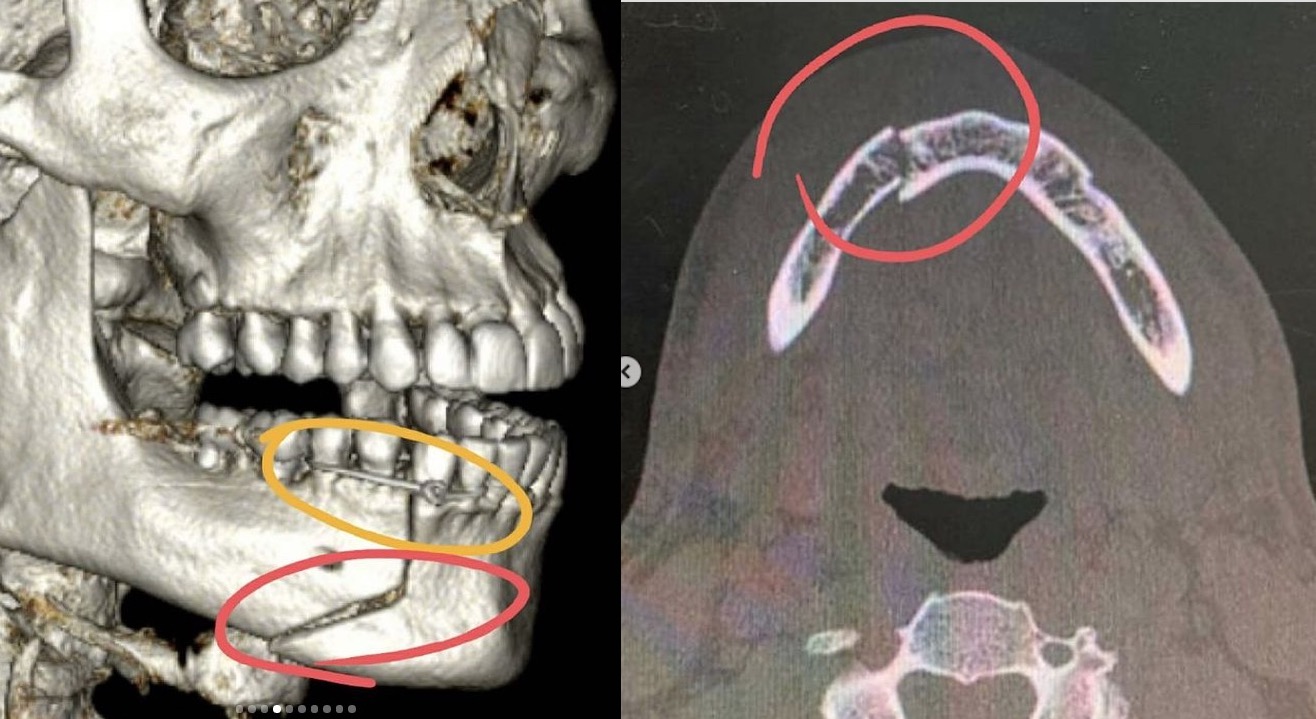

“Anunciaram há pouco que eu entrei numa briga em Alagoas, o que não é verdade. Foi muito triste o que aconteceu comigo. Vocês devem ter visto que eu dei entrada na Santa Casa de Alagoas no final do ano por ocasião de um acidente na academia. Mas a verdade é que não foi um acidente e não foi na academia. Eu fui agredido covardemente, sem que eu pudesse reagir ou me defender. Eu estava com alguns amigos e, do nada, fui puxado pelas costas, pelo pescoço, jogado no chão e agredido. Vítima de socos e chutes no rosto, que levaram a uma fratura exposta na minha mandíbula. A impressão que eu tinha é de que minha boca estava pendurada naquele momento”, contou o ator.

“Pensava apenas na minha família, nos meus filhos. Fiquei com muito medo de ficar com sequelas pra sempre. Minha boca ainda tá torta, e ainda está muito inchado, muito roxo. (…) Agora vou precisar de descanso, acompanhamento clínico por um tempo, remédio e torcer para que não haja sequela nenhuma. Há muito o que se fazer ainda”, disse.